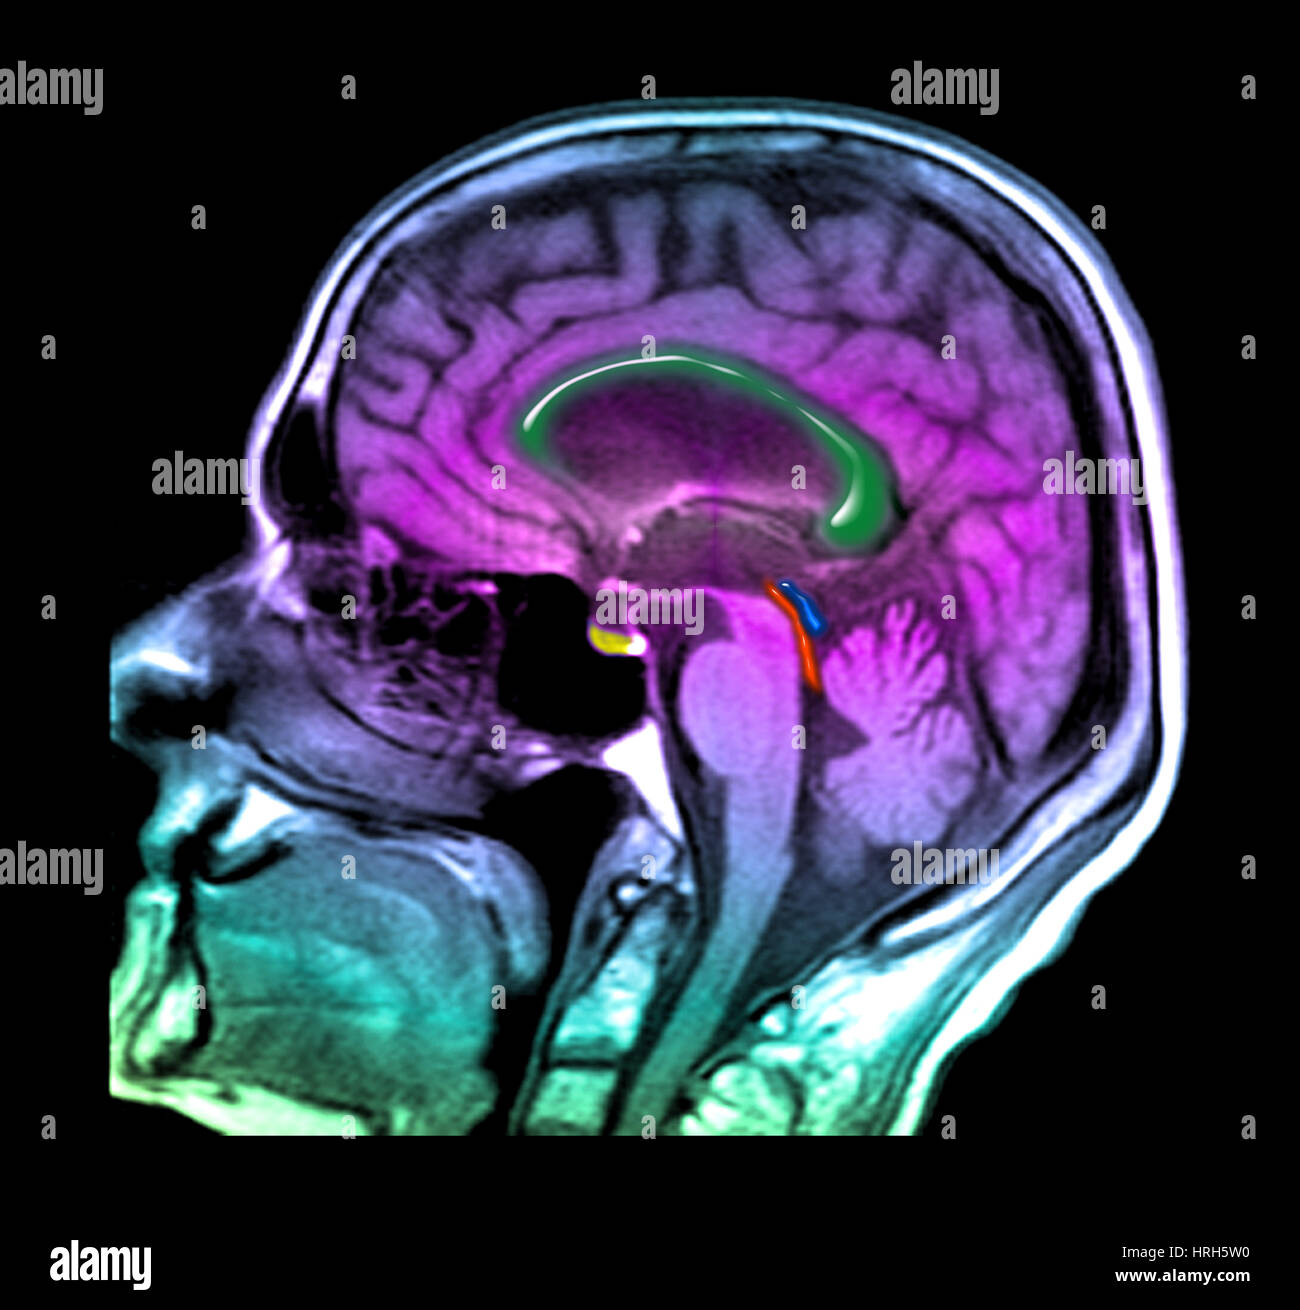

Source: matrizzzrb.pages.dev L'hydrocéphalie à pression normale Photo Stock Alamy , L'hydrocéphalie à pression normale (HPN) a été décrite pour la première fois en 1965 par Adams et Hakim L'hydrocéphalie à pression normale (« HPN ») est une affection neurologique rare, causée par une accumulation excessive de liquide céphalo-rachidien dans les ventricules (cavités) du cerveau

Source: terciartzsg.pages.dev Hydrocéphalie à pression normale une mise à jour Aerzteverlag medinfo AG , On imaging, it can be characterized both on CT and MRI by enlarged lateral and third ventricles out of proportion. L'incidence de l'hydrocéphalie à pression normale est de 5,5 personnes sur 100 000 par an

Source: lennixalo.pages.dev Hydrocéphalie chronique et autres pathologies chroniques du liquide cérébrospinal Fiche santé HCL , En raison de cette accumulation, les ventricules se dilatent et peuvent endommager ou détruire les tissus cérébraux. L'hydrocéphalie à pression normale (HPN) a été décrite pour la première fois en 1965 par Adams et Hakim